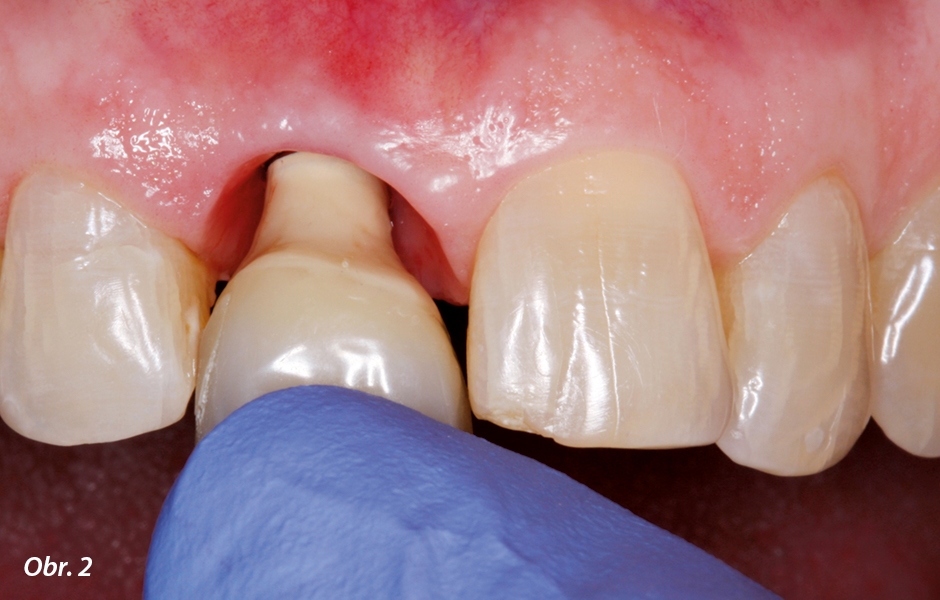

K výrobě tohoto otiskovacího členu byla opatrně z úst pacientky vyjmuta dlouhodobá provizorní náhrada našroubovaná na nitrokostním implantátu (obr. 2). Na první pohled byla patrna dobře vytvarovaná architektura měkkých tkání, u které byly jak vertikální výška volného okraje gingivy vestibulárně v místě implantátu, tak i horizontální tloušťka tkání srovnatelná se situací na vedlejším levém středním řezáku (obr. 3). Po dobu sejmutí dlouhodobého provizoria, potřebnou pro výrobu individualizovaného otiskovacího členu, bylo zabráněno kolapsu intraorálních měkkých tkání našroubováním konfekčního vhojovacího válečku, jehož objemové nedostatky ve srovnání s provizorní korunkou byly kompenzovány cirkulárním vstříknutím silikonu, používaného na skusové registráty, kolem obvodu válečku.4

Po uvolnění šroubovaného spojení byla laboratorně zhotovená provizorní korunka opatrně sejmuta z nitrokostního implantátu

Architektura měkkých tkání, vytvořená pomocí dlouhodobého provizoria, je srovnatelná se situací kopírovaného přirozeného levého středního řezáku